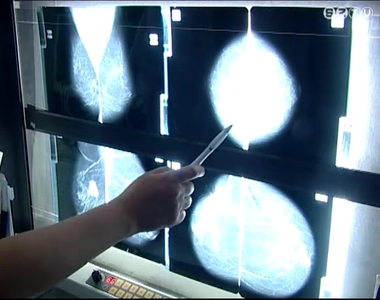

A Markusovszky-kórház radiológiáján évente tízezer szűrést végeznek, és nagyjából 150 rosszindulatú elváltozást találnak. Minél korábban fedezik fel a daganatot, annál nagyobb a gyógyulási esély.

"Itt látható a jobb emlőben egy 1 cm-es rosszindulatú daganat, ez egy korai emlőráknak minősül. Ezzel szemben egy idős nőbeteg jobb emlőjében egy

előrehaladott, nagyméretű daganat található, ezt már nem szeretjük szűrésen megtalálni."